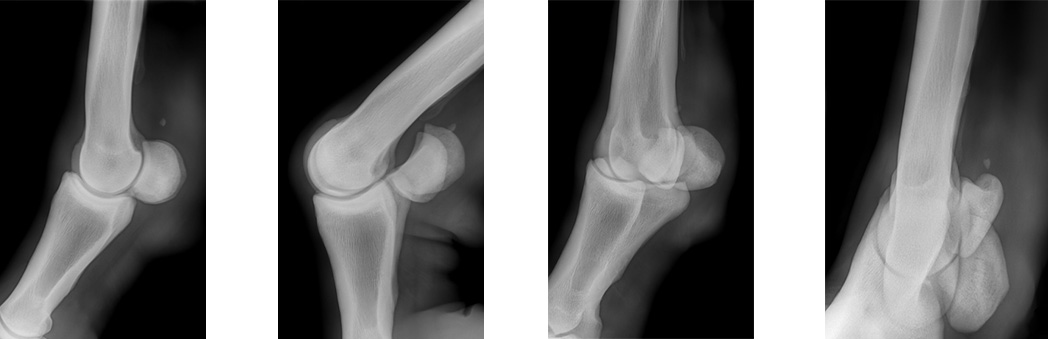

Radiography

Radiography :

Radiographs of fetlock revealed osteoarthritic change indicated by sesamoid remodelling and evidence of dorsomedial remodelling of proximal P2.